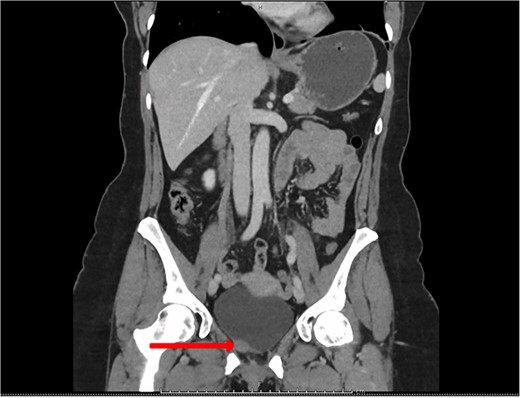

Blood tests included full blood count revealing all parameters within normal limits, eGFR >90 ml/min/1.73m2, Creatinine 64 umol/L and urea 4.5 mmol/L. Urine cultures were negative for infection. Ultrasound revealed a normal-appearing urinary tract, with both kidneys normal in size, shape and echopattern. Flexible cystoscopy revealed only a cystic lesion near the bladder dome which instigated further investigation; subsequent contrast-enhanced Computerized Tomography (CT) abdomen-pelvis scan showed a potential urachal remnant consistent with the flexible cystoscopy finding. In addition, a 1.5-cm-soft tissue structure was identified near the bladder neck which was not clearly seen initially at cystoscopy (Figs 1 and 2).

CT urogram (axial view) revealing a 1.5 cm thickening at the level of the right lateral bladder neck, and a 1-cm-soft tissue thickening at the bladder dome.